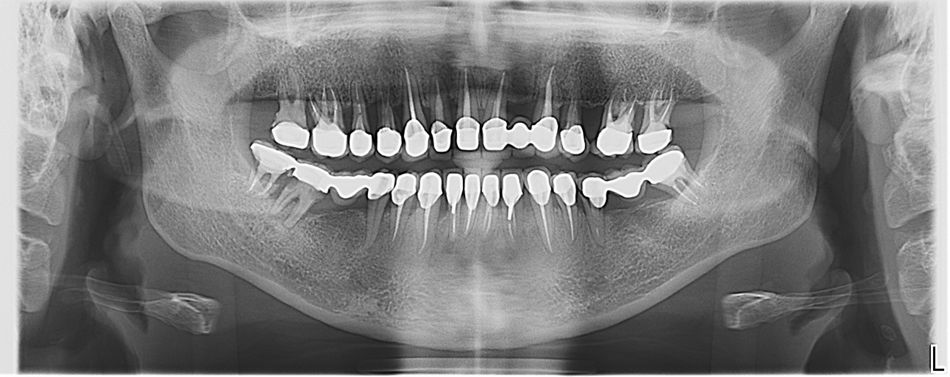

Иллюстрация 25

Ортопантомограмма спустя год после завершения реабилитации пациентки. (Илл. 25)